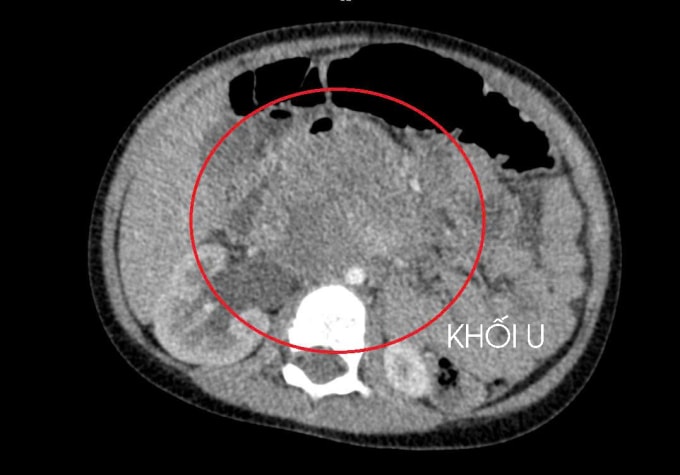

Bé trai thường xuyên đau bụng quanh rốn, bác sĩ phát hiện u lớn chèn ép thận bé do ung thư tinh hoàn di căn.

Ngày 10/1, các bác sĩ Bệnh viện đa khoa Hùng Vương cho biết bé đau bụng trong thời gian dài song gia đình ở vùng xa khó tiếp cận y tế và khám sàng lọc. Khi bé nhập viện, khối u đã chèn ép thận, kết quả sinh thiết ung thư tinh hoàn di căn gan và phổi. Nguyên nhân do tinh hoàn không xuống bìu, nằm trong ổ bụng từ khi sinh ra, âm thầm phát triển mà không có biểu hiện rõ ràng trong những năm đầu đời.